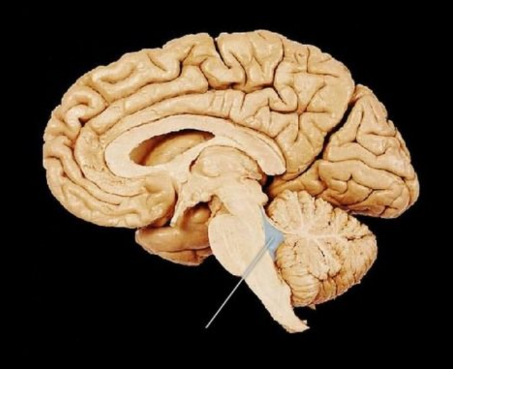

corpus callosum

ventriculus IV

Vermis cerebelli

Aquaeductus mesencephali

Thalamus Dex.

hypophysis

ventriculus III

komora III